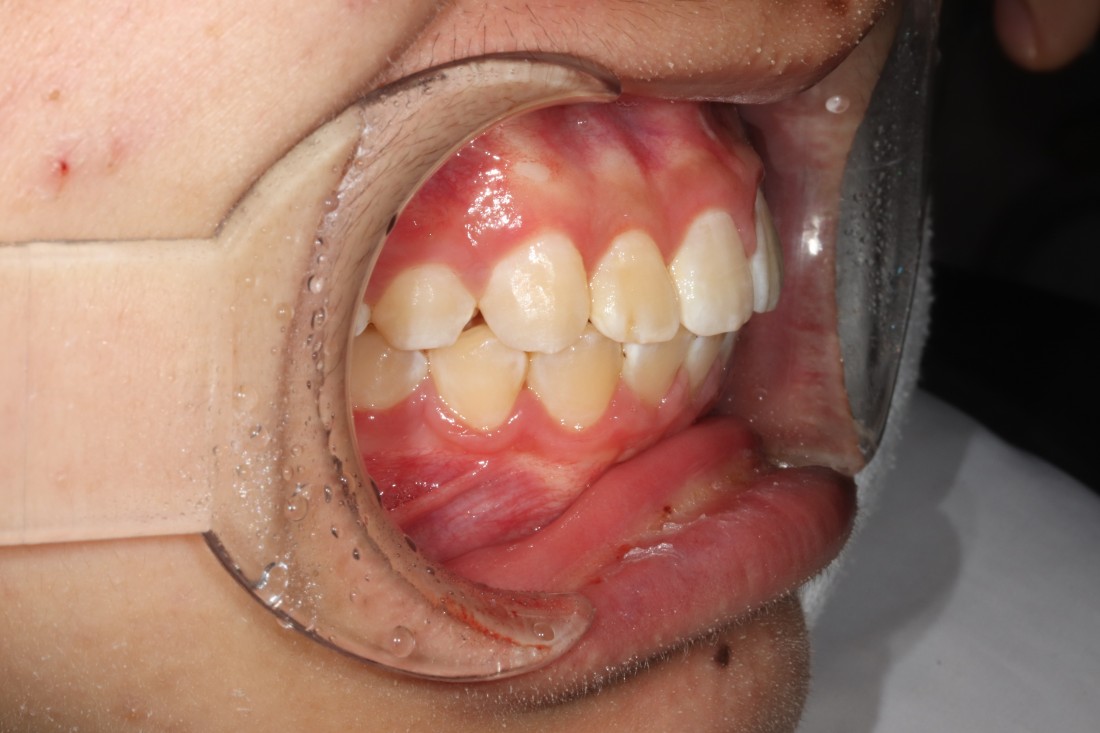

발치교정이 필요할 때 발치부터

충치치료, 필요한 경우 임플란트 진료까지

각 분과별 전문의 대표원장이

각각 본인의 파트를 맡아서

최상의 치료계획을 세우고 있습니다.

특히 충치진료와 임플란트의 경우

교정진료의 속도에 맞추어서

함께 진행하는 경우

훨씬 치료 효율이 좋기 때문에

다른 치과에 가지 않아도

교정전문의 진료와 전문의 충치치료가

함께 가능한 광산구 교정치과를

선택하는 것이 좋습니다.